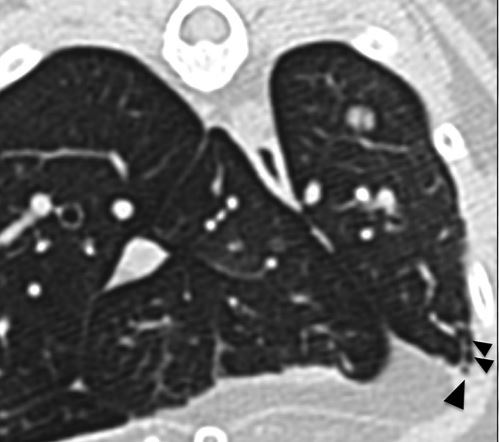

Oh et al: CT bronchial collaspe normal dogs: What was the percentage of collapse seen in the bronchi regularly in this paper?

A

Oh et al: CT bronchial collaspe normal dogs: What bronchi were most clinical affect?

Left cranial (dorsal and ventral segments) and left caudal lungs

The left cranial dorsal segment and the left caudal had collapse of over 50% on all of them.